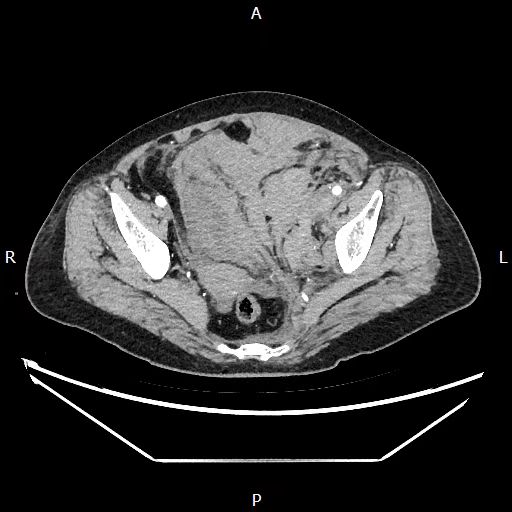

经过一天一夜的密切监护,患者生命体征稳定,转回普通病房继续治疗。经过CT复查,积血已经基本吸收,但危机仍未解除。因血肿压迫形成的左下肢深静脉血栓,如同“定时炸弹”,随时可能脱落并顺着静脉系统回流,阻塞肺动脉血管,引发致命性肺栓塞。

血肿已基本吸收